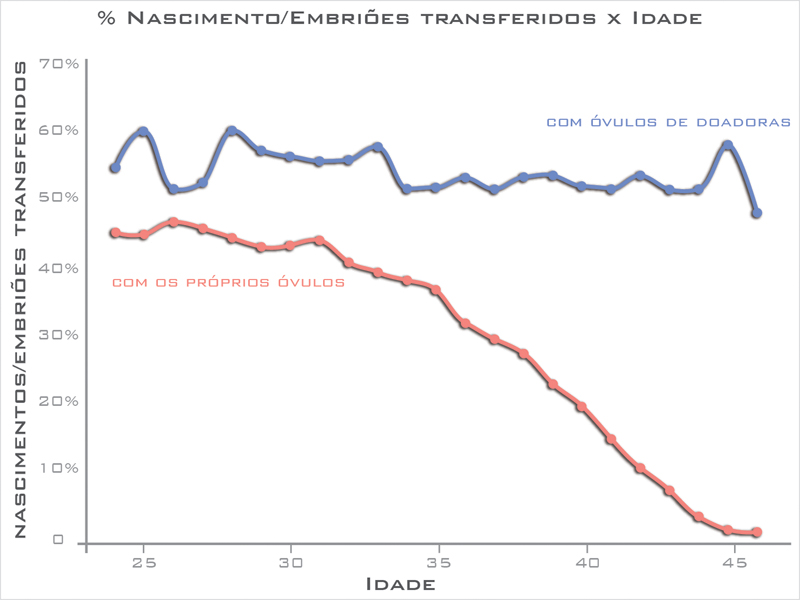

O tratamento com óvulos doados tem grande chance de sucesso. Dentre todas as técnicas, é a que resulta em maior chance de gravidez, chegando perto de 60% de sucesso.

O sucesso dessa técnica não depende da idade da receptora, diferente da FIV com óvulos próprios, onde este é o fator principal a ser avaliado, conforme mostra o gráfico abaixo.

A chance da mulher engravidar com seus próprios óvulos tem relação direta com a idade da mulher, porém com óvulos de doadora essa chance mantem-se mais ou menos constante mesmo com o avanço da idade da mulher.